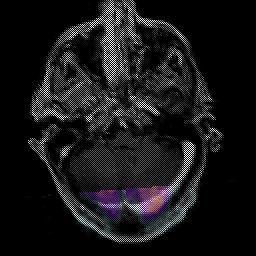

Glioma Overlay -- Slice #4

[Home][Help][Clinical] Slice 4